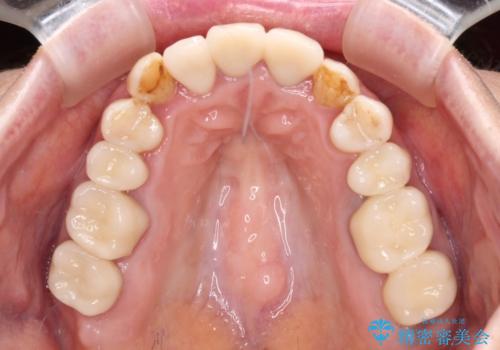

矯正治療後にはオールセラミッククラウンにて補綴治療を行うこととしました。

歯冠長延長術を行ったことで、自然な形態かつ清掃性の高いセラミッククラウンを装着することができました。

全顎的に治療を行ったため、治療期間も費用も負担は大きくなりましたが、統一感のある仕上がりとなりました。